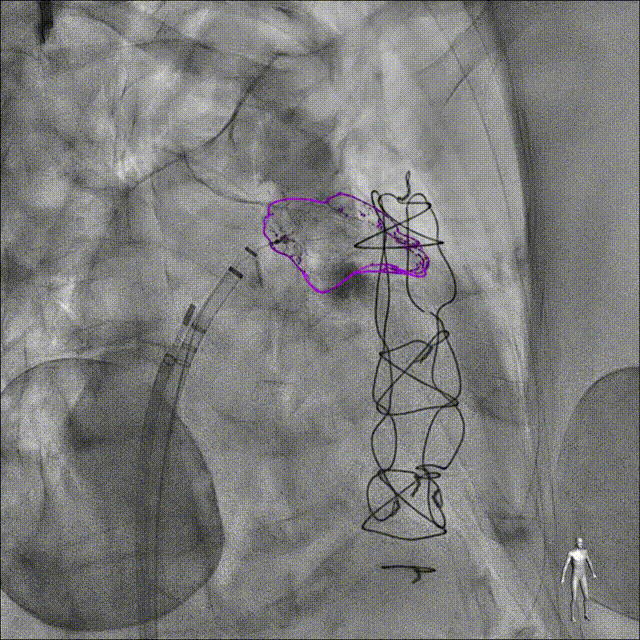

系统会自动识别并标注关键解剖点,例如冠状动脉开口、心房间隔以及人工瓣膜的最佳着陆区域。在术中,这些标记会随着实时影像动态更新,提供持续的导航支持。

“塞”式封堵器标记测量

主动脉根部结构标记

病例2:WATCHMAN封堵器LAAO